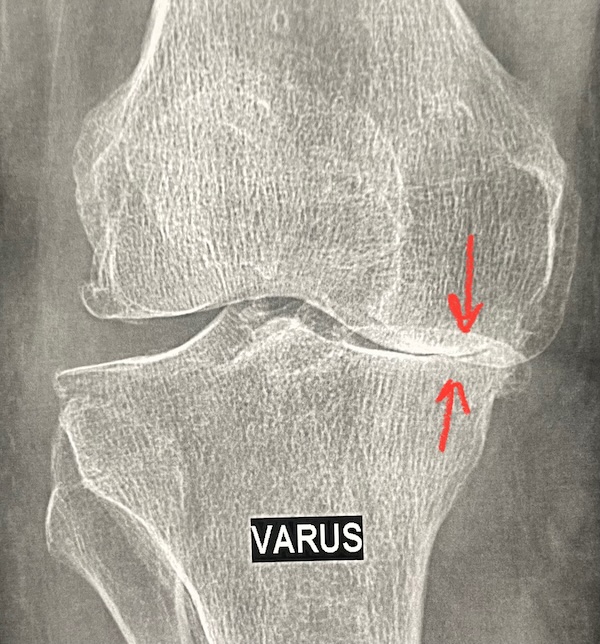

Sur le dessin de cette coupe de l'articulation, on peut observer l'os de part et d'autre, recouvert de cartilage. Quand le cartilage s'use, l'os n'est plus recouvert ni protégé par le cartilage : c'est la définition de la chondropathie, puis de l'arthrose. Son traitement chirurgical consiste à poser une prothèse, c'est-à-dire enlever ce qui reste de cartilage (la chondropathie) et une fine épaisseur d'os, pour pouvoir poser la pièce de la prothèse sur l'os restant.

Sur ces deux coupes irm, vous pouvez voir la différence d'épaisseur du cartilage; le vide formé par l'usure est rempli de liquide synovial (blanc sur l'irm).